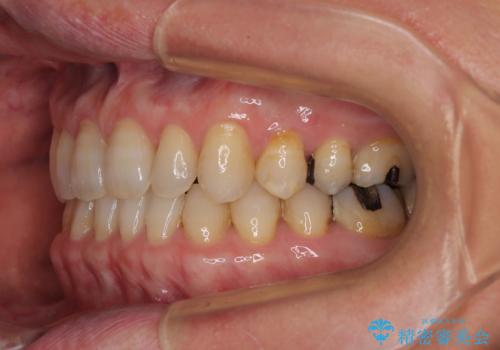

- 前歯のデコボコと隙間の空いた歯列を気にして来院された患者様です。

下顎前歯が隠れるほどのディープバイトにより、強い咬合力と突き上げで上顎歯列に隙間が空いている状態でした。

手前に傾斜している奥歯をワイヤー装置で立ち上がらせ、咬み合わせの高さを挙上することで突き上げを解消し、空隙歯列を改善していくこととしました。